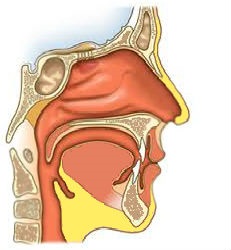

Nas - a persoanelor implicate în respirație, simțul mirosului, precum și efectuarea rezonator și funcții de protecție. Anatomic distins nas extern și cavitatea nazală. Nasul exterior este format din schelet-os cartilaj uman, care de sus este acoperit de mușchi și piele. cavitatea nazală frontală comunică cu exteriorul printr-o deschidere nazală (nares), spate - cu nazofaringe prin nări interne (coanal).

Septul nazal este format de placa verticală a osului etmoid, vomer si cartilajul separa cavitatea nazală în dreapta și două jumătăți. În sept divizie anteroinferioara este bogat in vasele de sange din zona Kisselbaha (eliberarea zonei nas sânge).

Cavitatea nazală sunt patru pereți: o laterali (lateral), interior (medial), superioare și inferioare. Pe peretele lateral al cornetul nazal sunt aranjate, care împart cavitatea nazală la superioară, mijlocie și inferioară o pasajelor nazale. Cel mai mare este turbinate inferior, coajă de mijloc și de sus sunt excrescențe ale osului etmoid.

pasajul nazal superior comunică cu sinusul sfenoid si posterior nara mediu sinusurile etmoidale os - cu maxilar (maxilar) și sinusurilor frontale, iar partea din față și a sinusurilor mijloc a sinusurilor etmoid. Nasul inferior în timpul unei conducte de deschidere nasolacrimal. cavitatea nazală a membranei mucoase este acoperit epiteliu ciliat format compus din celule ciliate si calciforme, mucina asigurarea transportului. În zona superioară a pasajului nazal (regiunea olfactivă) situată închiderea periferică a nervului olfactiv.